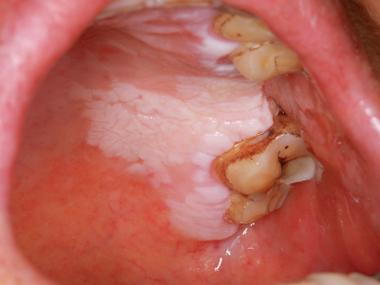

口腔腮帮子有条白棱是何问题?

(图片来源网络,侵删)

可能性二:口腔白斑病

这是一种癌前病变,需要高度重视,但并非所有的口腔白斑都会癌变。

- 长期局部刺激: 长期吸烟、咀嚼槟榔、饮酒、咀嚼烟丝等是主要诱因,长期的机械刺激(如残根、假牙)也可能诱发。

- 表面粗糙,呈白色或灰白色,形态不一,可以是斑块、皱纹状或颗粒状。

- 通常没有明显的疼痛感,这是它容易被忽视的原因之一。

- 去除刺激因素后,白斑可能不会自行消失,甚至会增厚、变硬。

可能性三:扁平苔藓

这是一种常见的、原因不明的慢性炎症性口腔黏膜病,可能与免疫、精神压力、药物、感染等多种因素有关。

- 典型的表现是“珠光白色条纹”或“网状白纹”,像“蕾丝花边”一样,有时也会表现为白色斑块或丘疹。

- 常常伴有口腔黏膜的糜烂、溃疡,此时会感到明显的疼痛,尤其在吃刺激性食物时。